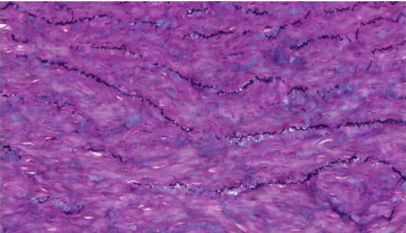

Masson染色

1.Masson三色染色法

用途及原理:称马松染色,经典的结缔组织染色法,用于鉴别胶原纤维和肌纤维。对肝硬化和肝炎导致的纤维增生、肾脏疾病诊断有重要价值。染色原理基于染料分子大小和组织渗透性。淡绿或苯胺蓝分子量大,染色后肌纤维红色,胶原纤维绿色或蓝色,便于区分。